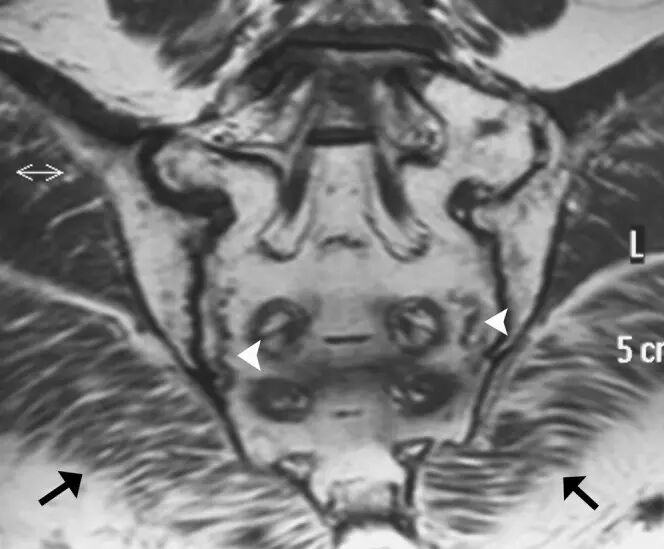

![]()

图8.26岁女性多发性肌炎,呈现双侧下肢疼痛和肌肉无力。(a)大腿的轴向T2加权的MR图像显示在股外侧肌,中间肌,内侧肌和股直肌(箭头)的异常,广泛的羽状水肿。注意保持正常的肌肉结构。T1加权成像(未显示)在受影响的肌肉中未显示信号改变或萎缩,或在此情况下有助于诊断。(b)两腿的冠状动脉脂肪抑制的T2加权的MR图像还在小腿的肌肉(箭头)中显示广泛的水肿信号。右腓肠肌的内侧头显得幸免(箭头)。